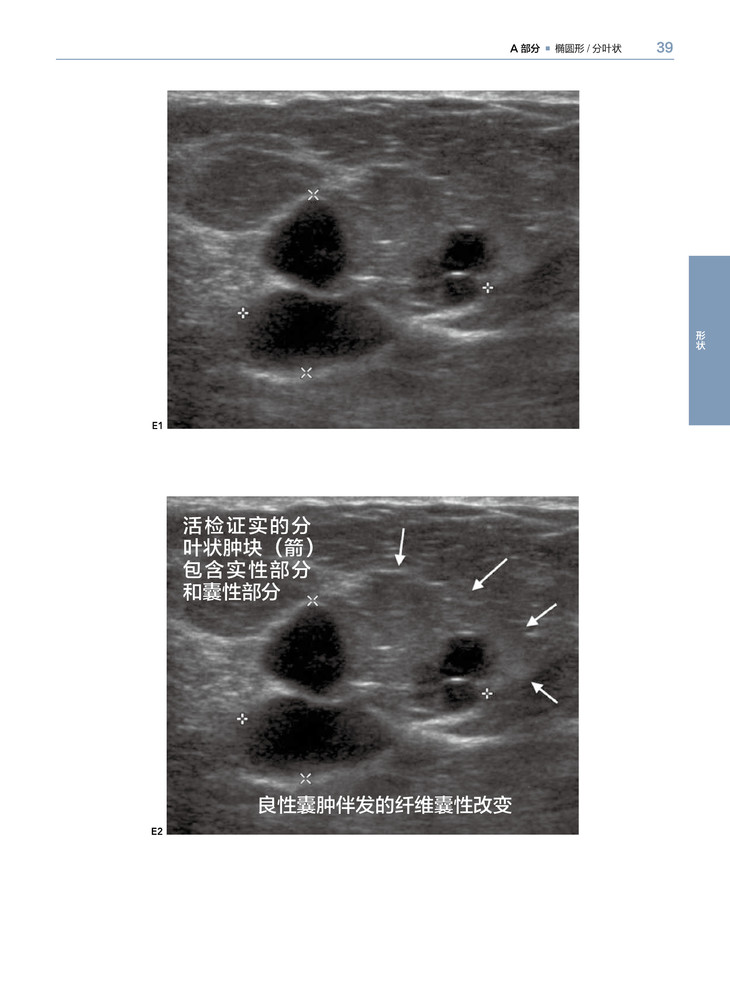

乳腺X线摄影和超声影像是乳腺影像检查最常用的两种方法。本书针对临床经常出现的有关乳腺癌影像表现,进行全面分析、归纳。乳腺癌主要是以三种形式表现的:肿块、钙化和结构变形。这本书主要分成以上3个主要部分,第四部分主要包括一些与恶性乳腺癌相关的重要影像表现。全书以病例为主,一共有400多个病例,文字简练,图片清晰,有病例的影像检查图,病理图,代表性强,能为各级影像科、乳腺科医生提供宝贵的参考价值。